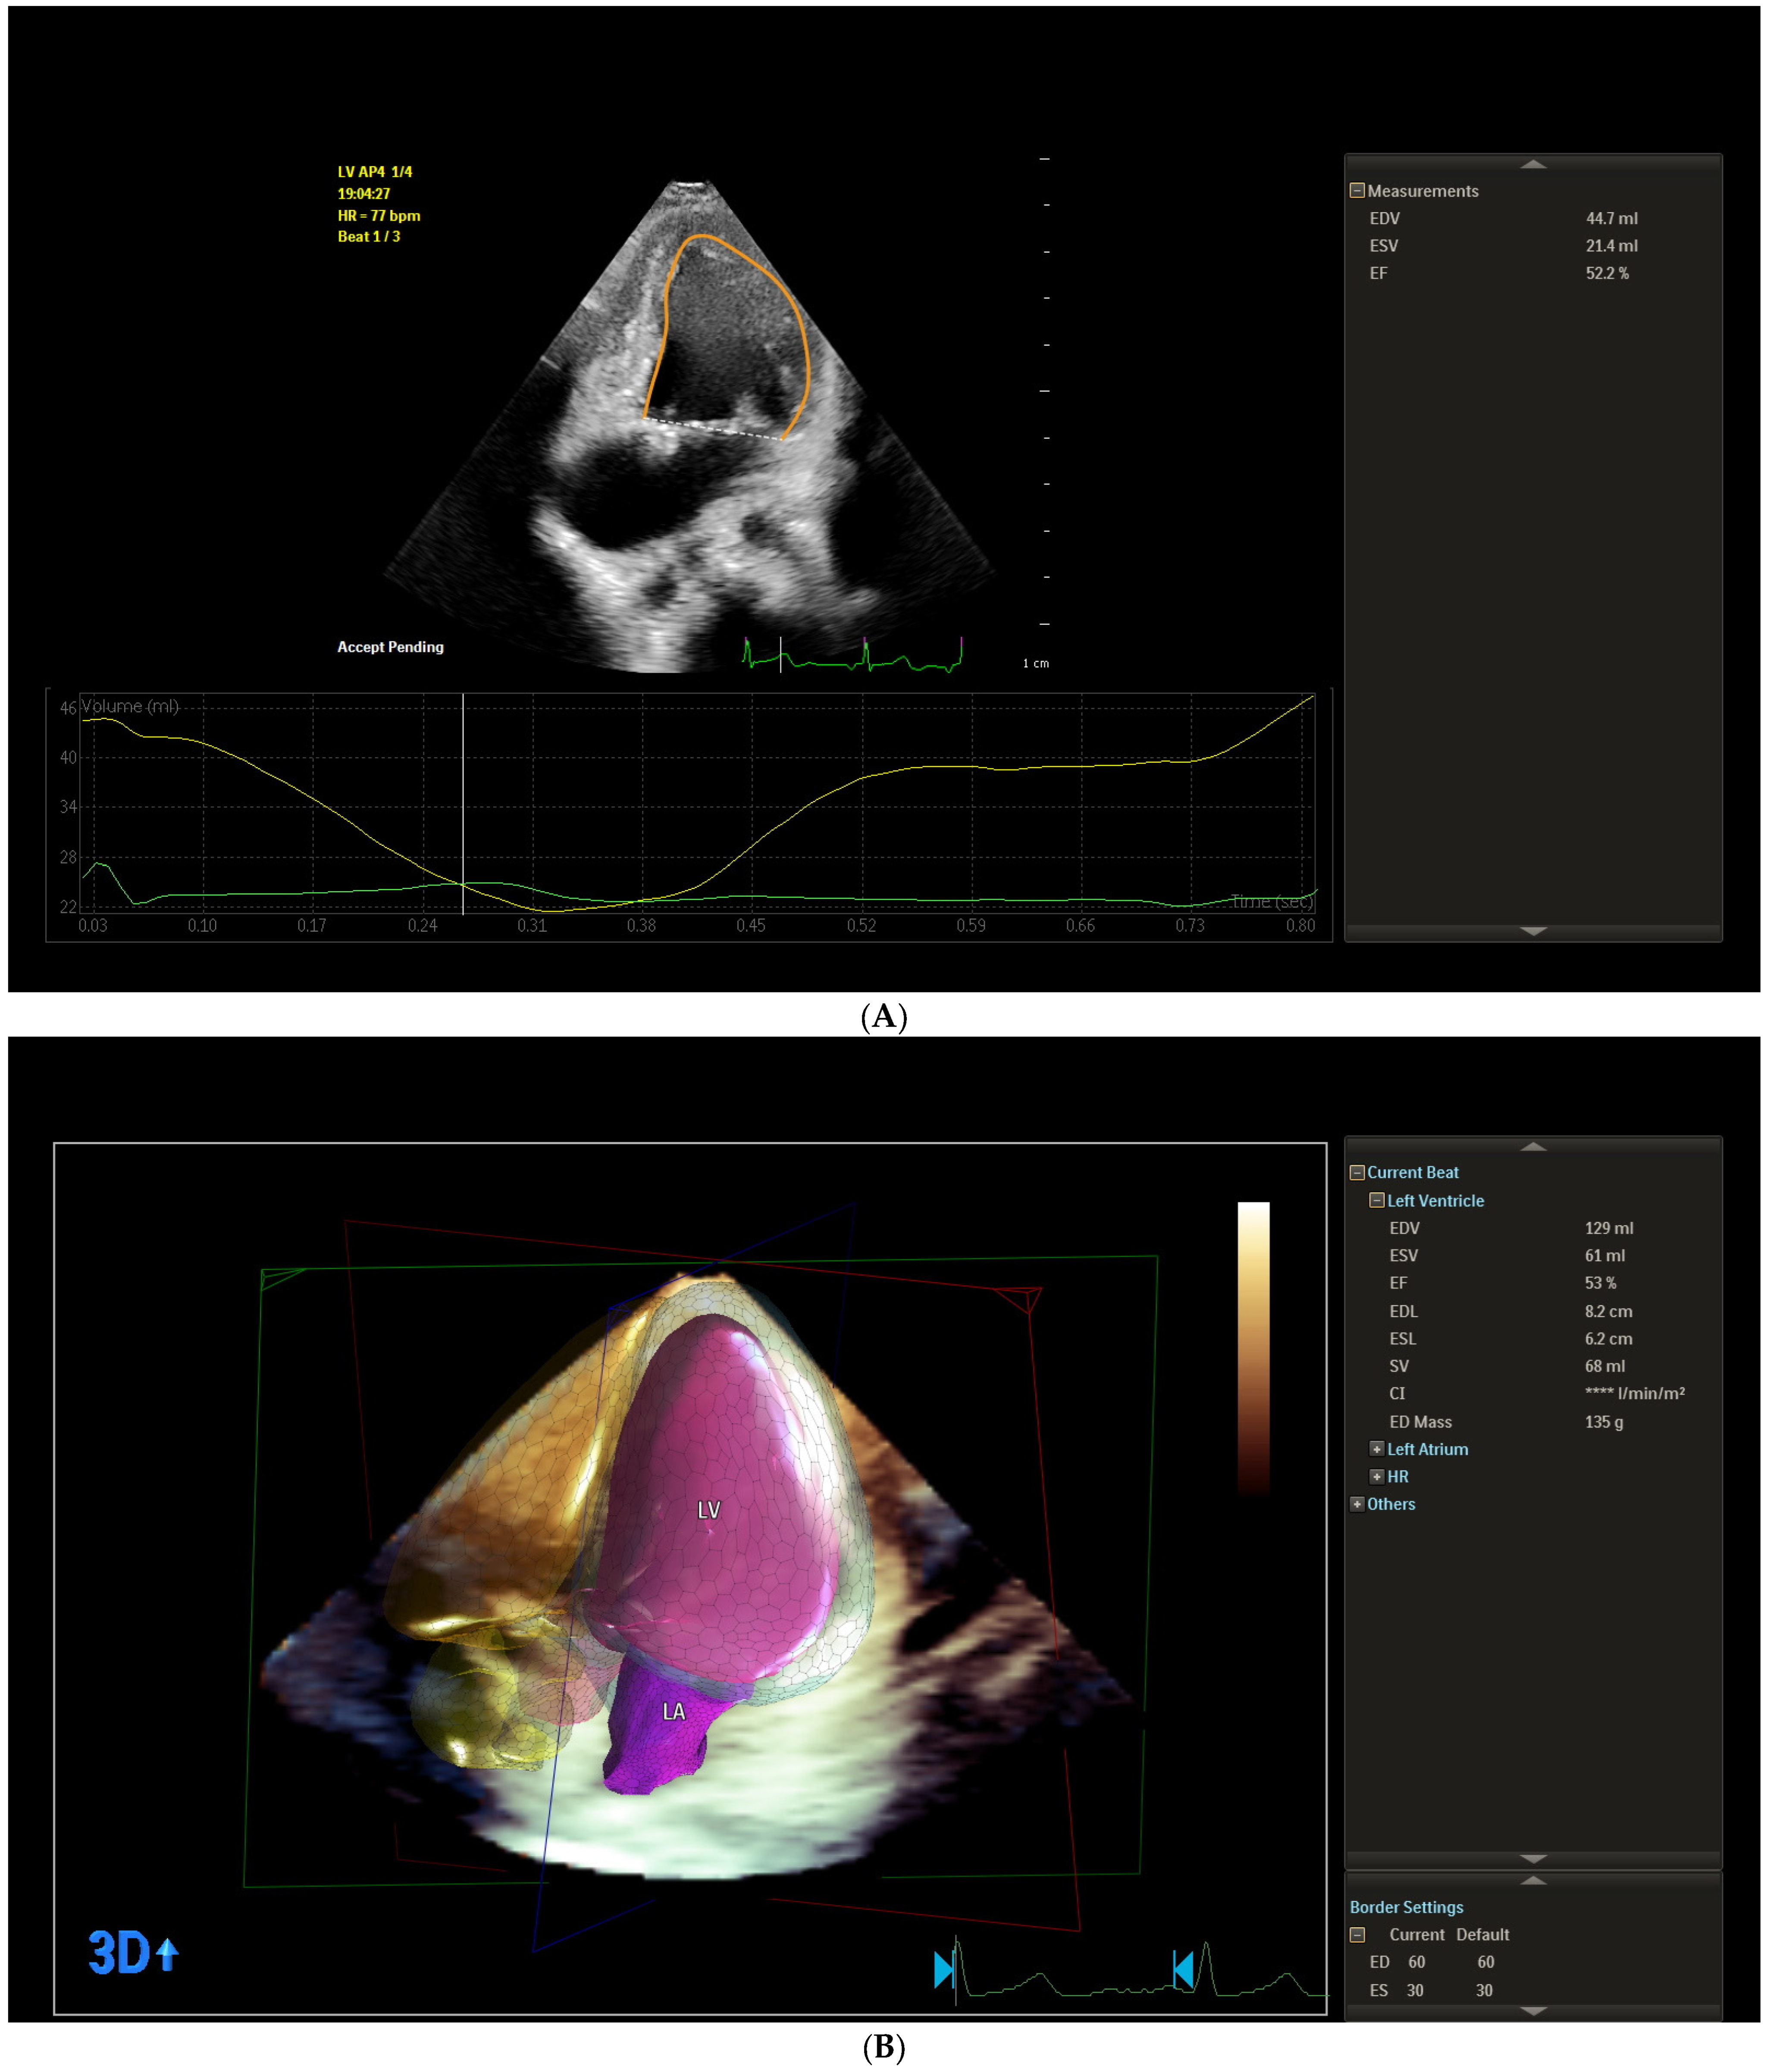

2.2.3. Speckle Tracking Acquisition and Analysis

3.5. Corelations Between Conventional, Two-Dimensional Echocardiographic Global Left Ventricle Longitudinal and Left Atrium Strain Indices

| LASr_ED (%) | 49.26 (16.26) | 26.01 (9.19) | <0.0001 * (b) | <0.0001 * |

| LAScd_ED (%) | −36.93 (12.85) | −17.09 (8.74) | <0.0001 * (a) | <0.0001 * |

| LASct_ED (%) | −12.21(6.47) | −10.50 (8.65) | 0.3685 (a) | 0.3856 |